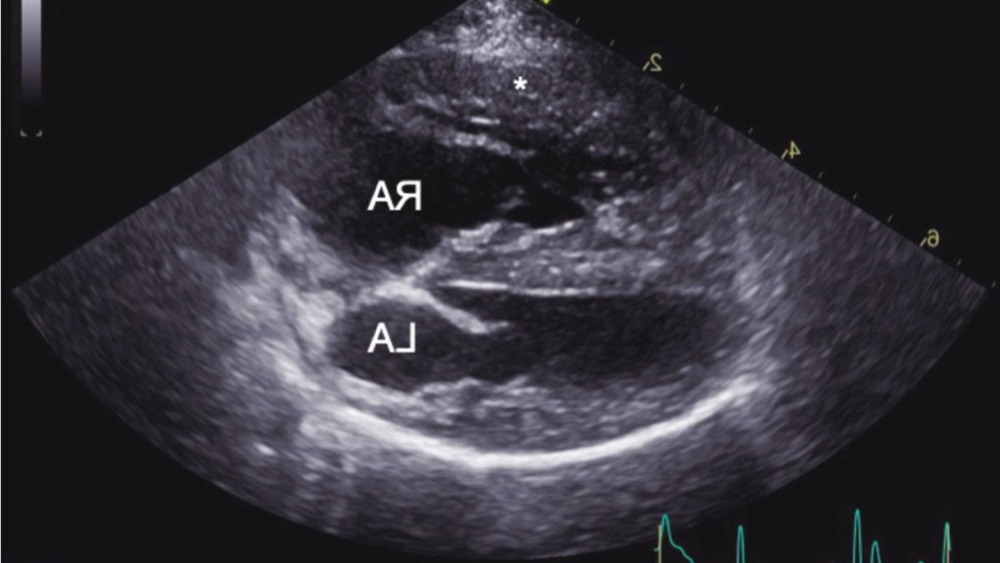

Echocardiography and why it matters

An ultrasound of the heart (echocardiogram) is usually the key test used to assess the probability of pulmonary hypertension and to look for underlying cardiac disease. It can estimate pulmonary pressures using Doppler measurements and can show typical right-heart changes that occur with sustained high pressure.1, 3

It is worth knowing that echocardiography is widely used in dogs because direct measurement of pulmonary artery pressure (right heart catheterisation) is rarely performed outside specialised settings. Good clinicians interpret ultrasound findings alongside the dog’s signs, exam, and other tests.1